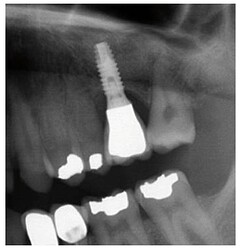

Preoperative panoramic X-ray view.

Sinus membrane integrity as established by endoscopy.

Postoperative panoramic X-ray view.

Panoramic X-ray view one year after prosthetic loading.